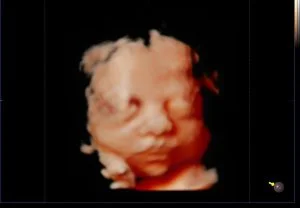

Como são as imagens vistas no exame?

Aqui está um exemplo de como será a visualização do bebê durante o exame: